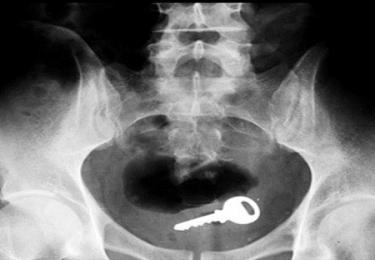

Rất nhiều người hỏi rằng sao hậu môn tôi có những vật gì đó lạ? Như thế là thế nào? Các chuyên gia cho rằng hiện tượng hậu môn có vật lạ có thể là do bệnh trĩ, rò hậu môn, nứt kẽ hậu môn hay áp xe hậu môn… thực tế hậu môn có những gì đó chỉ là câu nói thông thường của mọi người, là cách thể hiện hiện tượng đang gặp, bởi vì người mắc bệnh không biết phải gọi như thế nào, có nhiều người mắc phải còn rất hoang mang, lo sợ. Nhằm giảm bớt lo lắng cho bệnh nhân, các bác sĩ của Phòng khám Đa Khoa Quốc Tế Cộng Đồng chỉ ra một vài phương pháp phòng tránh như sau:

Làm thế nào để phòng tránh dị vật ở hậu môn